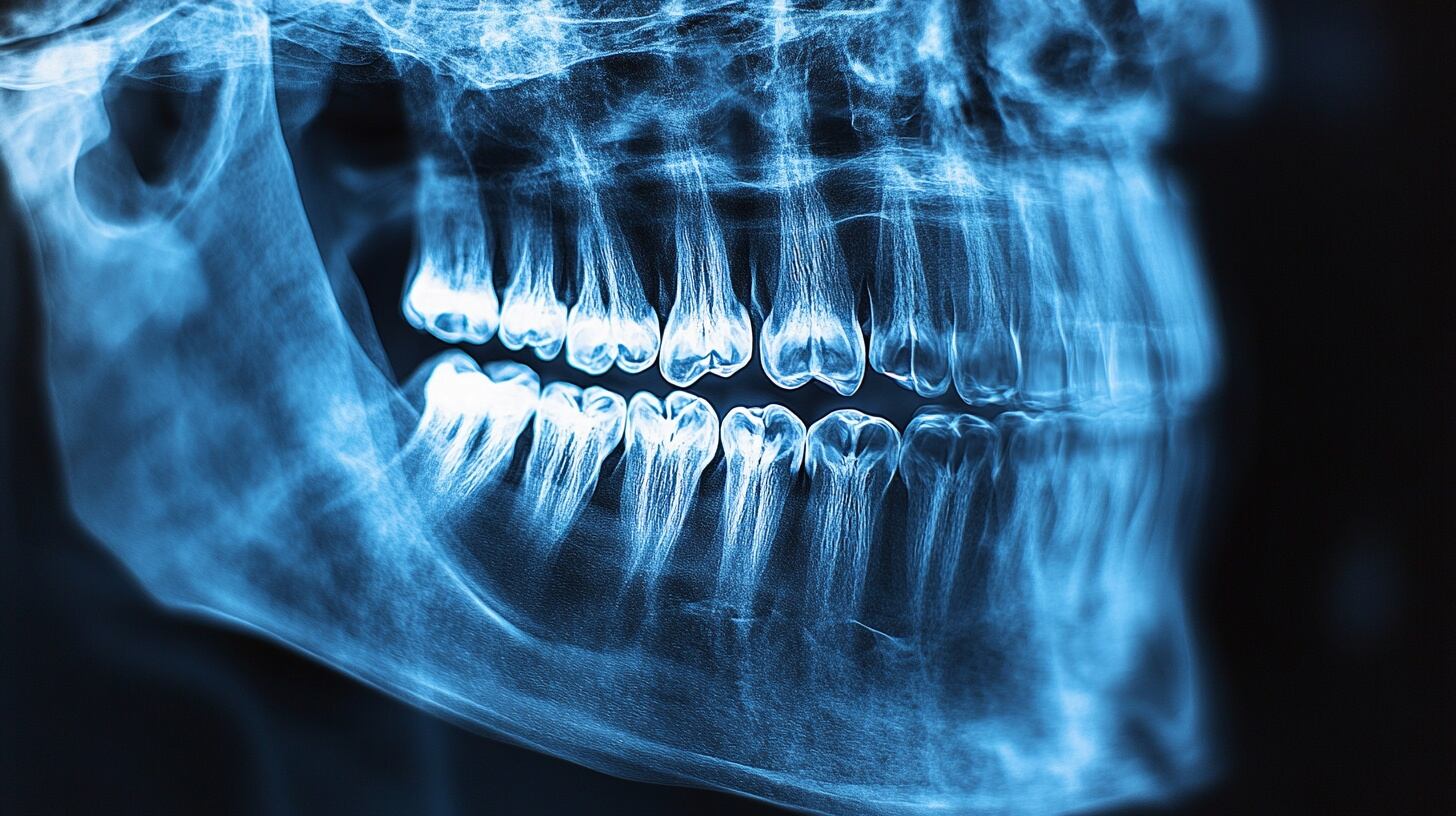

Wu señaló que los síntomas iniciales de la enfermedad de las encías suelen pasar desapercibidos, ya que en muchos casos no generan dolor. Entre los signos tempranos se encuentran encías enrojecidas, inflamadas o que sangran con facilidad, especialmente durante el cepillado o el uso de hilo dental. Otros indicios incluyen mal aliento persistente, sensibilidad gingival, retracción de las encías y pérdida de dientes. Ante la presencia de cualquiera de estos síntomas, recomendó una evaluación inmediata por parte de un profesional dental.